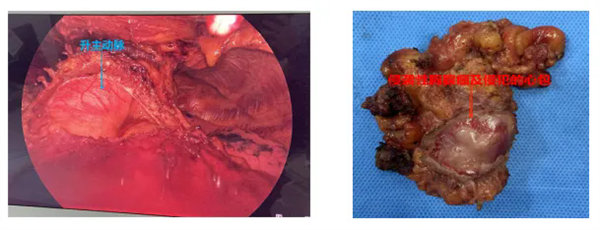

在麻醉手術(shù)科陳治富主任團(tuán)隊(duì)的大力支持下,術(shù)中緊密合作,精細(xì)游離病灶,在狹小的空間下(三個(gè)小戳卡孔直徑分別為2cm、0.5cm、0.5cm)小心謹(jǐn)慎的切除受侵犯心包(切除心包后顯露出了主動(dòng)脈根部、心包內(nèi)肺動(dòng)脈部分、心耳等重要結(jié)構(gòu)),最后在充分游離出雙側(cè)無(wú)名靜脈的前提下切除胸腺上極及兩側(cè)心包外脂肪,同時(shí)對(duì)無(wú)名靜脈及上腔靜脈旁淋巴結(jié)進(jìn)行清掃,達(dá)到完整切除全胸腺的目的。術(shù)后,患者在醫(yī)護(hù)團(tuán)隊(duì)的精心照料下,恢復(fù)情況良好,無(wú)并發(fā)癥發(fā)生。